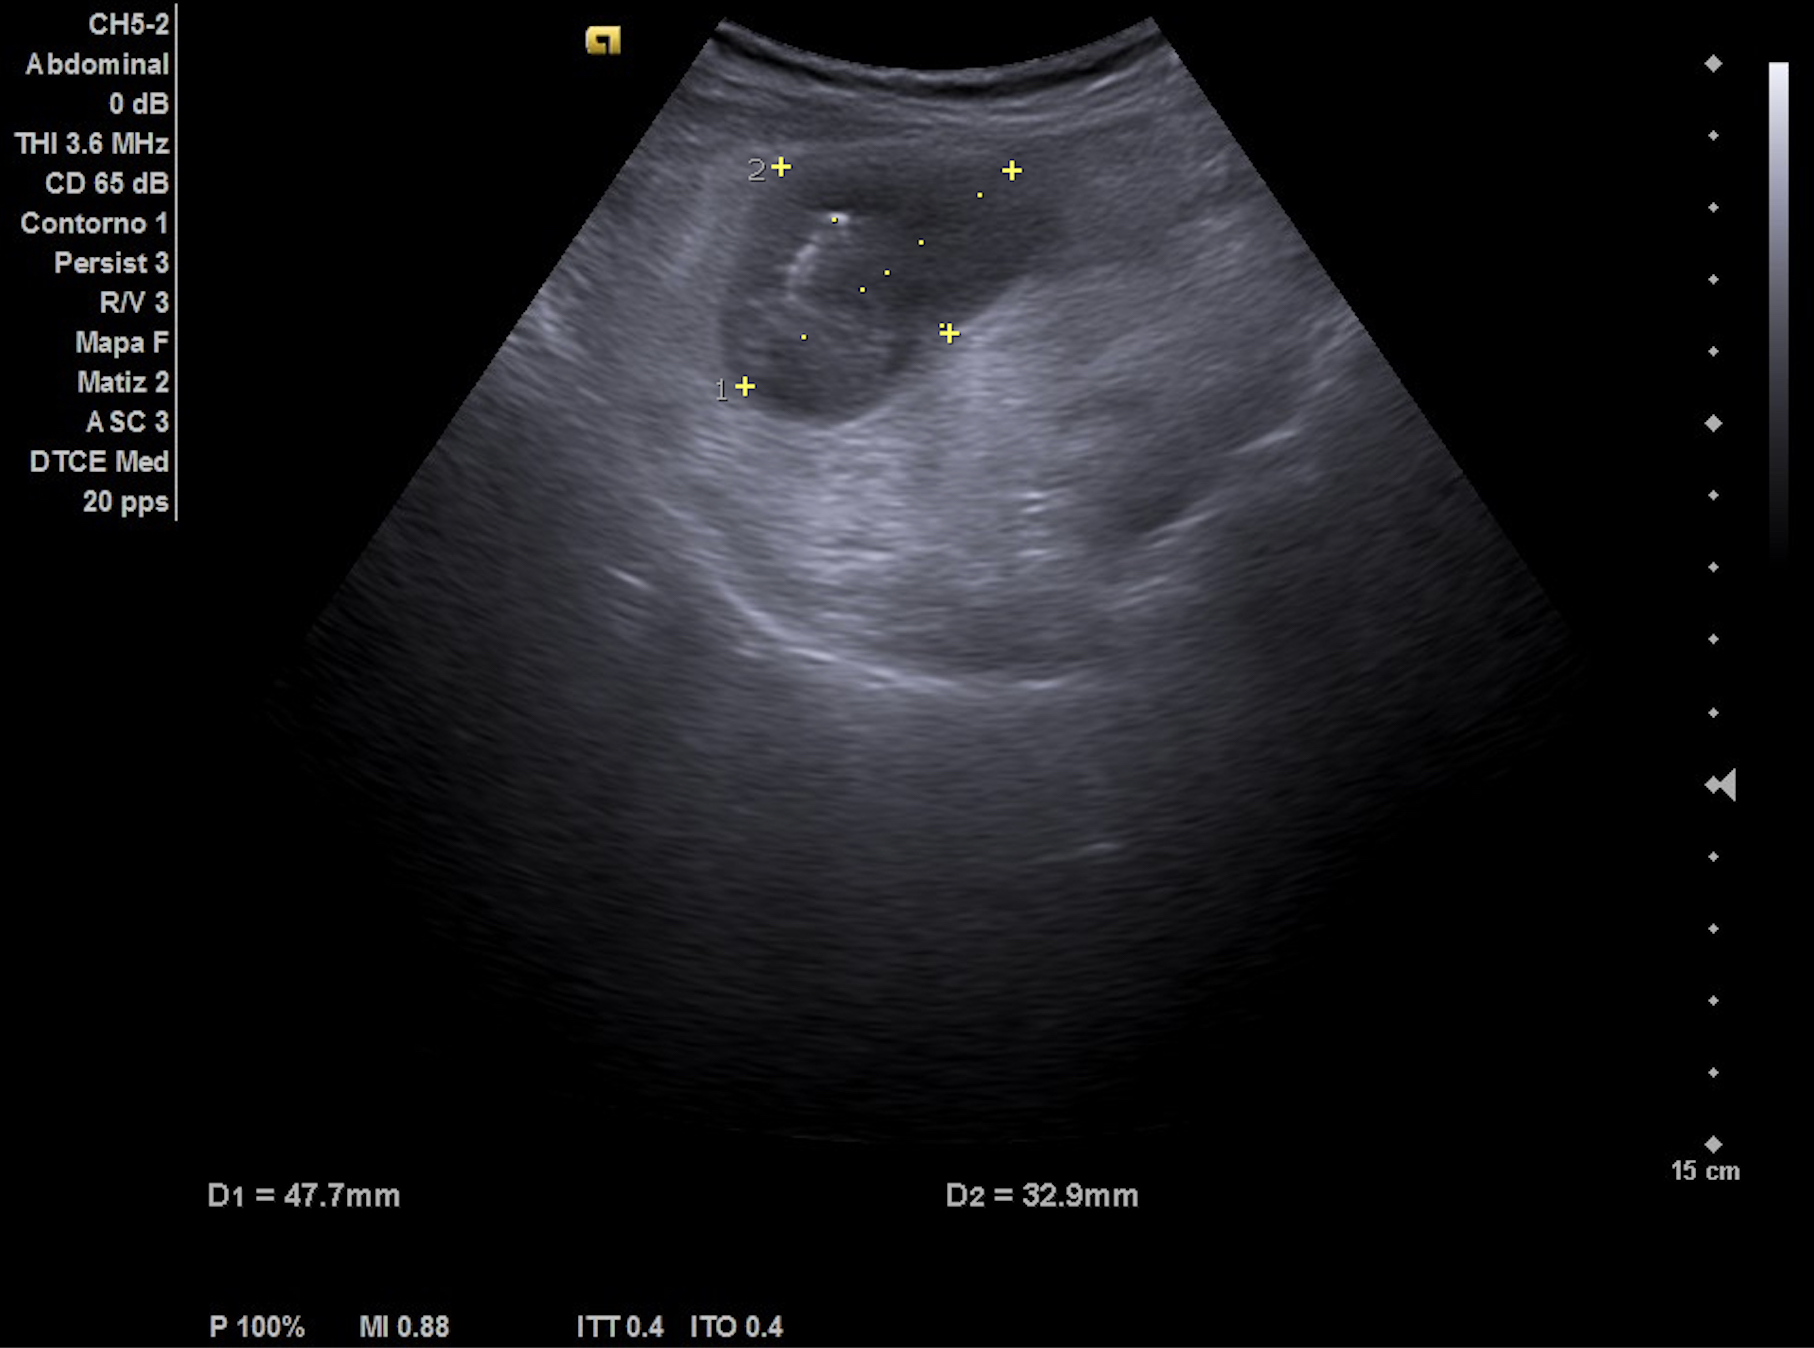

- Hígado de tamaño y eco-estructura normal. Riñón derecho normal. Imagen localizada anterior a riñón derecho, redondeada-ovalada, hipoecoica con zonas hiperecoicas en su interior, vascularizada probablemente compatible con signo de pseudo-riñón con sospecha de neoplasia de colon.